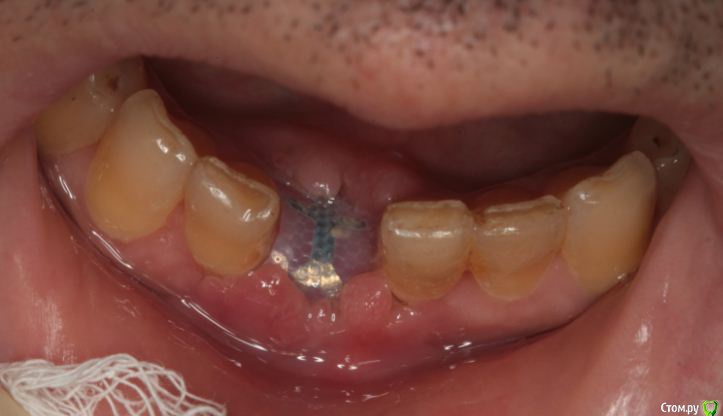

Endorphin Опубликовано 11 августа, 2015 Автор Поделиться Опубликовано 11 августа, 2015 Только что на осмотре был похожий пациент от коллеги. 2 Ссылка на комментарий

Чертков Александр Опубликовано 11 августа, 2015 Поделиться Опубликовано 11 августа, 2015 Только что на осмотре был похожий пациент от коллеги. onemore.JPGНу тут явная "недомобилизация" и неадекватное ушивание. 1 Ссылка на комментарий